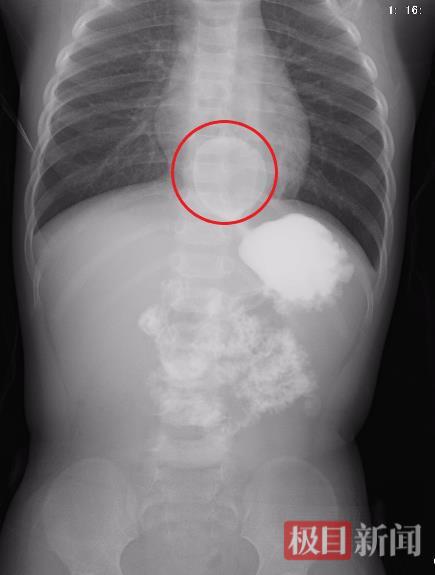

食道中有一颗被“泡发”的水宝宝(科室供图)

“若是诺如病毒引起的呕吐,通常在对症治疗后会缓解,但佑佑的呕吐病程已长达五天,且一进食就吐,肯定不是单纯的诺如病毒感染。”据佑佑的管床医生黄帅介绍,入院后,佑佑接受了一系列检查,发现心肌酶指标有所升高,心脏彩超检查还发现一处“疑点”:患儿的心脏右后方有个类圆形无回声区,疑似“囊性包块”。

结合患儿的呕吐症状,医生团队敏锐推测:心脏问题可能是“障眼法”,消化道问题很可能是“幕后真凶”。果然,消化道造影检查结果证实了医生的判断,佑佑的食管下段惊现一个直径约3厘米的圆形物体,边界清晰。考虑到孩子才1岁,儿科医生怀疑这很可能是误吞的异物。